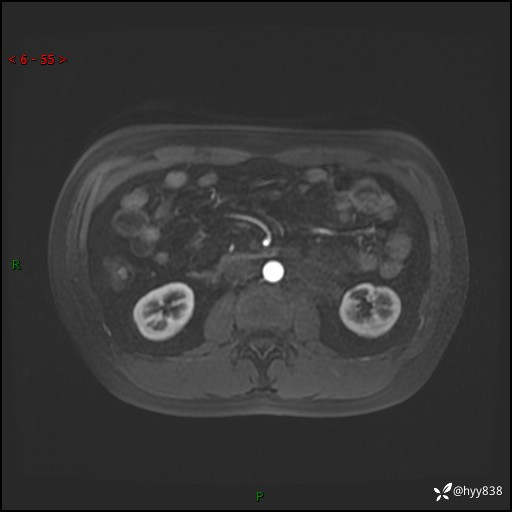

现病史:患者3月余前检查发现左侧腹膜后占位,大小约3.7*4.9cm,平素无腰疼,无肉眼血尿,无尿频尿急等不适,当时未特殊处理,在门诊复查CT提示左侧腹膜后占位,门诊拟“左侧腹膜后占位”收入院。 起病以来,患者精神佳,饮食、睡眠良好,大小便正常,体力体重无明显变化。

MRI增强